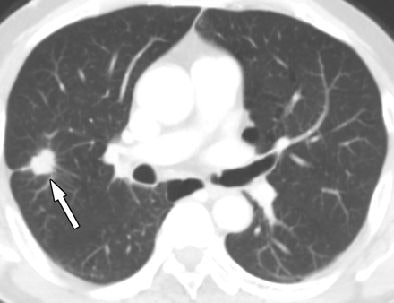

| Axial cardiac CT images in a 63-year-old man with solitary pulmonary nodule visible in full field-of-view only. Above, full-FOV image shows 2-cm spiculated nodule (arrow) in right upper lobe. Below, limited-FOV image obtained at same level shows nodule is collimated from view. This lesion was confirmed to be adenocarcinoma after right upper lobectomy. Images republished with permission of the Radiological Society of North America from Radiology (Vol. 255:2, pp. 369-376). |

The mean diameter of the cancers was 23 mm ± 10.5 (range, 5-42 mm), and the most common location was the right upper lobe (n = 13, 36%). Adenocarcinoma was the most common histology, seen in 86% of patients (31 of 36) with lung cancer. Of the 34 non-small cell lung cancers detected at CT, 23 (68%) were resectable, including 16 of the earliest stage IA cancers, the authors wrote.

"The detection of lung cancer was significantly different between the limited- and full-FOV cardiac scanning examinations, between limited-FOV cardiac scanning and full-FOV thoracic scanning, and between the full-FOV cardiac and thoracic scanning examinations," the authors wrote (p < 0.0001 for all comparisons).

Importantly, of the 26 cancers detected at CT, four (11%) were seen with a limited FOV (covering the heart plus 1-4 cm). Meanwhile, 19 (53%) were seen with a wider FOV that extended from outer rib to outer rib and encompassed the entire lung parenchyma with the portion of the thorax that was imaged. Another 17 cancers (47%) could be detected only in full FOV at thoracic scanning, Kim and colleagues reported.

"Eighty-nine percent of lung cancers would have been missed with limited-FOV cardiac scanning," they wrote. "It is essential that the entire imaging dataset, including the full-FOV images, be evaluated at cardiac CT, because viewing in the limited FOV at cardiac scanning may result in the majority of lung cancers that could be detected on full-FOV images being missed."